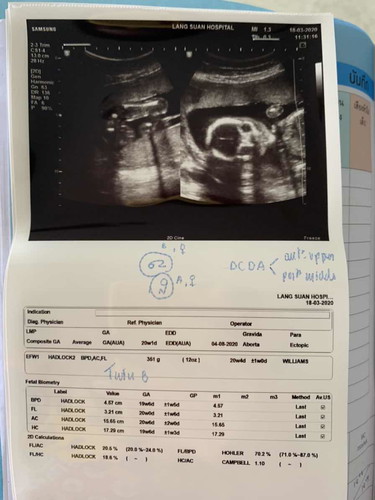

ช่วยดูน่อยค่ะ เพศอะไร

แบบนี้เพศหญิงไหมค่ะฝาแฝดค่ะ

น่าจะผู้หญิงนะคะแม่